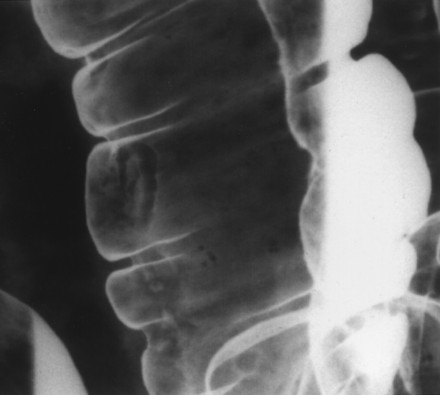

Có hai kỹ thuật chủ yếu chụp đại trực tràng thụt baryt là cản quang đơn (single contrast) và cản quang kép (double contrast) để bộc lộ các tổn thương niêm mạc, tổn thương trong thành đại tràng và tổn thương đè ép từ ngoài. Chụp cản quang đơn thường được dùng để đánh giá tắc đại tràng, rò đại tràng, chụp cho người già, bệnh nhân nặng, hoặc yếu sức. Chụp cản quang kép (Hình 1) thường được dùng để phát hiện các tổn thương nhỏ (<1cm), các bệnh viêm ruột, và đánh giá chi tiết hình ảnh trực tràng [2].

Các chi tiết giải phẫu X quang bình thường của đại tràng (xem Hình 1 và 2).

Hình 1. Chụp khung đại tràng.